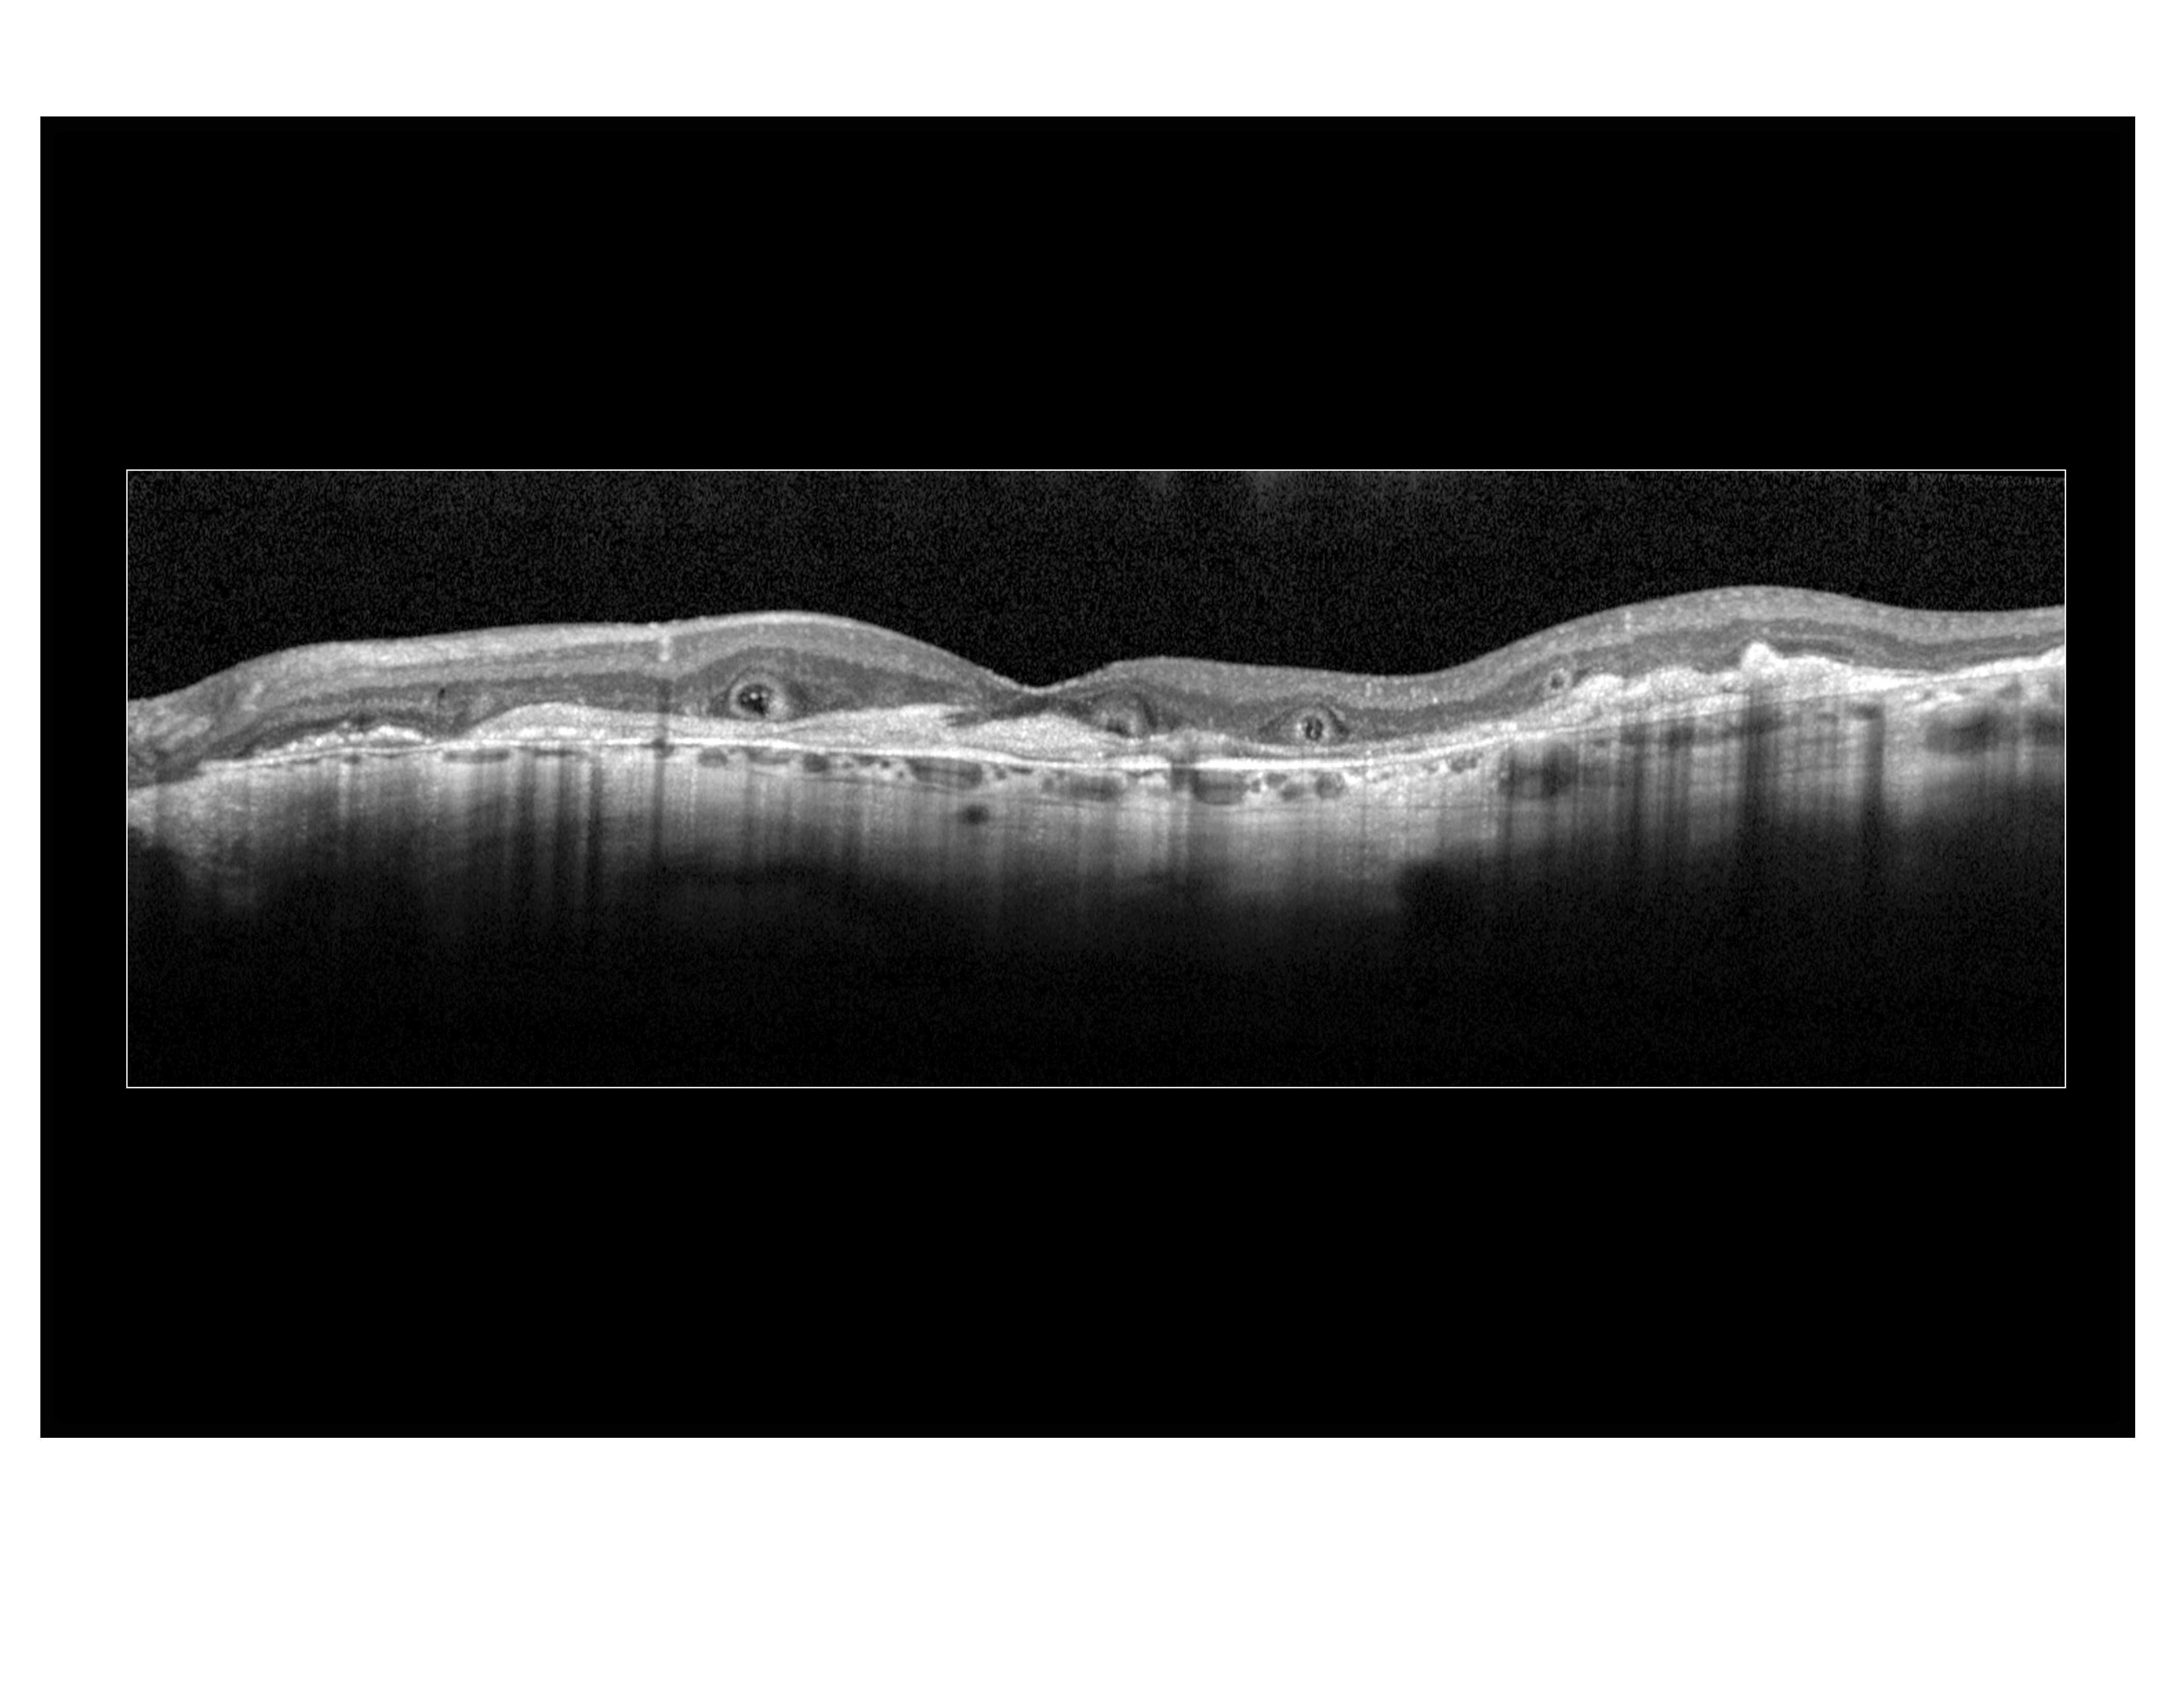

Outer Retinal Tubulation

Presented by Megan Walsh, CRA, OCT-C

This photograph received Honorable Mention in the category "Optical Coherence Tomography" and was displayed in the 2024 OPS Exhibit.